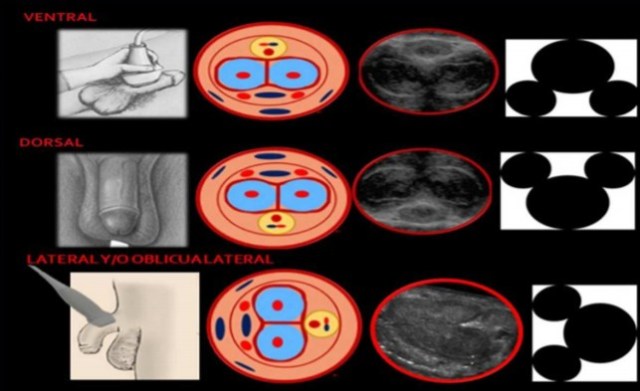

Cómo se realiza? La colocación del transductor puede variar. En la primer columna (plomo) tenemos un gráfico del abordaje, en la segunda (rosado) el esquema donde se representan las estructuras anatómicas, en la tercera (gris oscuro) una imagen ecográfica, y la última (blanco y negro) imagen la figura símil Mickey que nos recuerda de una manera práctica donde se ubican los cuerpos cavernosos con respecto al esponjoso en cada exploración. En la primer hilera tenemos la exploración ventral clásica, y luego las dos opcionales dorsal y laterales.